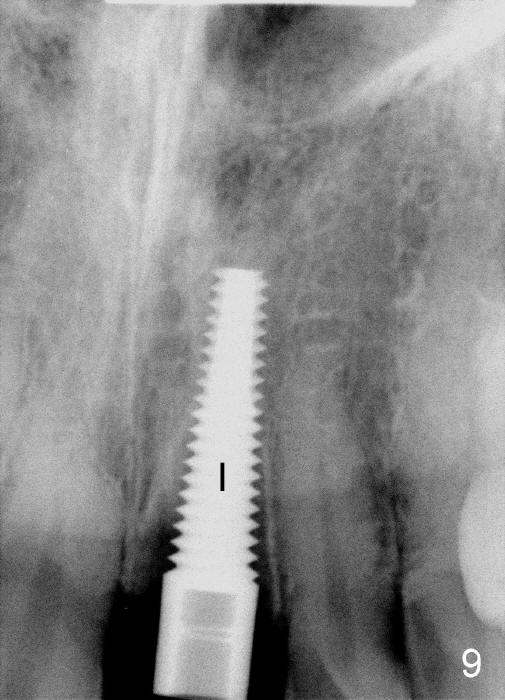

The upper right central incisor (Fig.1: #9) fractures subgingivally due to trauma for a 40-year-old man.  The incisive canal is large (I) and close to the root of the central incisor.  After extraction, the osteotomy (Fig.3b, 4: O) is made with 2 mm pilot drill (Fig.2: D) on the lingual wall (Fig.3a: L) of the socket (Fig.3a: S).  To push the incisive canal mesially, the osteotomy is enlarged by 3.5x21 mm and 4x21 mm tapered osteotomes (Fig.5,6: O).  Due to the lingual slope (Fig.7a arrow), the osteotome (blue outline) starts to deviate bucally.  To reduce this tendency, the coronal portion of the lingual slope is removed (Fig.7b: yellow circle).  The final implant (4.5x20 mm) is able to be placed as lingually as possible (Fig.7c, 8).

Bone expansion allows the implant (Fig.9 I) to have primary stability (insertion torque between 50 and 60 Ncm), since the cortex of the incisive canal is apparently intact.  Allograft is placed in the labial gap (Fig.10, 11 *) following installation of the abutment (A).  Finally an immediate provisional (Fig.10,12 P) is cemented.  Fig.13,14 are taken 8 days postop.  The patient returns 3 months postop (Fig.15,16).  Osteointegration appears to have occurred (Fig.15 arrowheads) and is more obvious 9 months postop (Fig.17).